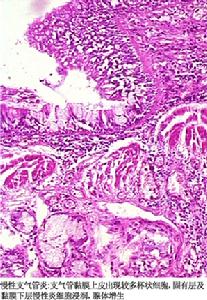

慢性阻塞性肺炎(obstructive pulmonary emphysema)又称阻塞性肺气肿